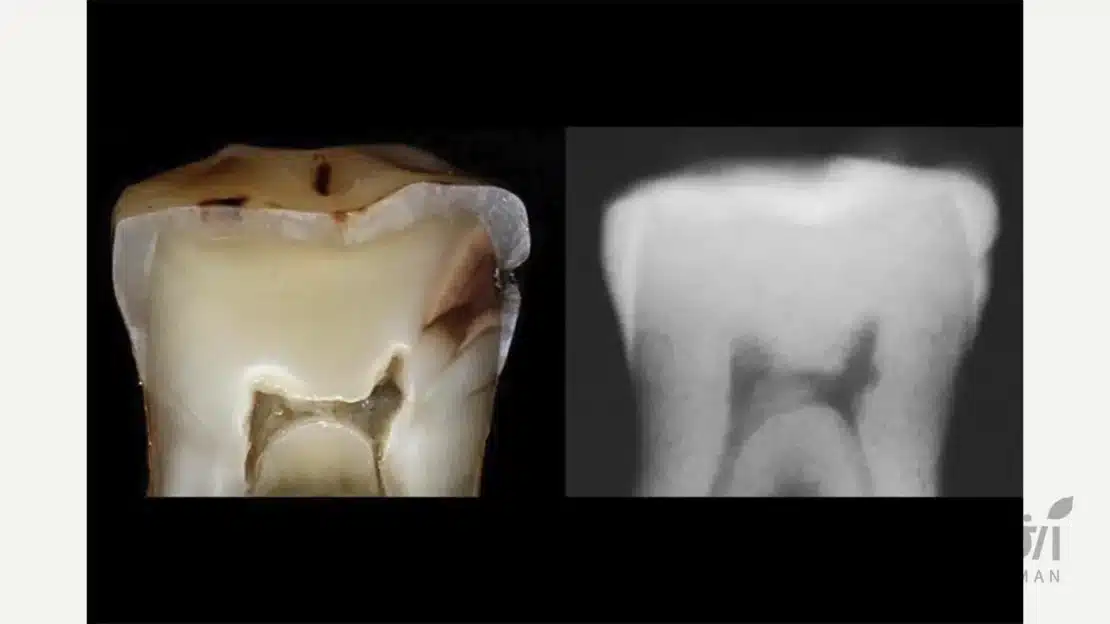

گاهی تغییر رنگ از داخل خود دندان منشا میگیرد و ترمیم به دلیل شفافیتی که دارد، آن را منعکس میکند. اگر دندانی که روی آن لمینت یا کامپوزیت انجام شده، دچار پوسیدگی جدید شود یا عصب آن از بین برود، دندان زیرین سیاه میشود.

این سیاهی از زیر لایه نازک کامپوزیت یا لمینت عبور کرده و به نظر میرسد که ترمیم تغییر رنگ داده است. در بررسی علت تغییر رنگ کامپوزیت و لمینت دندان، نباید از سلامت بیولوژیک بافتهای دندانی غافل شد.

خونریزی داخلی پالپ و عفونت دندان هم مطرح است

دندانهایی که ضربه خوردهاند یا قبلاً درمان ریشه شدهاند، ممکن است به مرور زمان تغییر رنگ دهند. مواد مورد استفاده در عصبکشی یا تجزیه شدن بافت عصب در داخل کانال، باعث تولید رنگدانههای تیره میشود.

چون کامپوزیت و برخی انواع لمینت (مثل ایمکس) شفافیت بالایی دارند، این تیرگی داخلی را نشان میدهند. تشخیص این مسئله بسیار مهم است چون درمان آن به جای تعویض ترمیم، انجام «بلیچینگ داخلی» یا درمان مجدد ریشه است تا علت تغییر رنگ کامپوزیت و لمینت دندان از ریشه حل شود.

پوسیدگیهای ثانویه در مرزهای ترمیم میتوانند رنگ دندان را تغییر دهند

اگر بهداشت دهان و دندان به درستی رعایت نشود، درزهای میکروسکوپی بین دندان و ترمیم محل تجمع میکروبها میشوند. پوسیدگی که در لبههای کامپوزیت ایجاد میشود، رنگ قهوهای تیره یا سیاهی دارد که به تدریج گسترش مییابد.